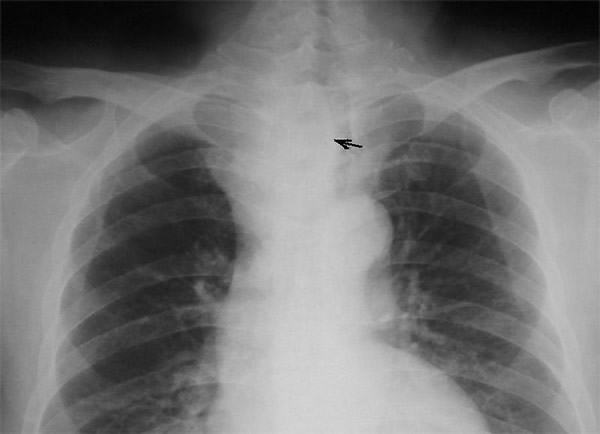

A 58-year-old Chinese man presented with a dry cough of three months’ duration. A chest x-ray at a local hospital revealed "a shadow in the superior mediastinum." A subsequent CT scan suggested "ectopic intrathoracic thyroid" (Figures 1 and 2). His physical examination revealed normal temperature and heart rate, without any signs of hyperthyroidism. Palpation of the neck revealed a non-tender, firm, fixed, and non-pulsatile 2 cm right inferior thyroid mass. A repeat chest x-ray confirmed a mass in the right anteromedial mediastinum, with smooth margins, tracheal compression, and deviation of the trachea to the left (Figure 3). Nuclear Tc99 thyroid scan revealed a cold nodule in the right inferior thyroid gland extending below the sternum (Figure 4). The values of total thyroxin 3 (TT3), total thyroxin 4 (TT4), free thyroxin 3 (FT3), free thyroxin 4 (FT4), and thyroid stimulating hormone (TSH) were all normal. Due to the suspicion of malignancy and to avoid the development of tracheomalacia, surgery was performed to remove the mass.

Figure 1: The arrow indicates the middle mediastinal mass. Figure 2: The arrow indicates the right middle mediastinal mass, trachea compressed.